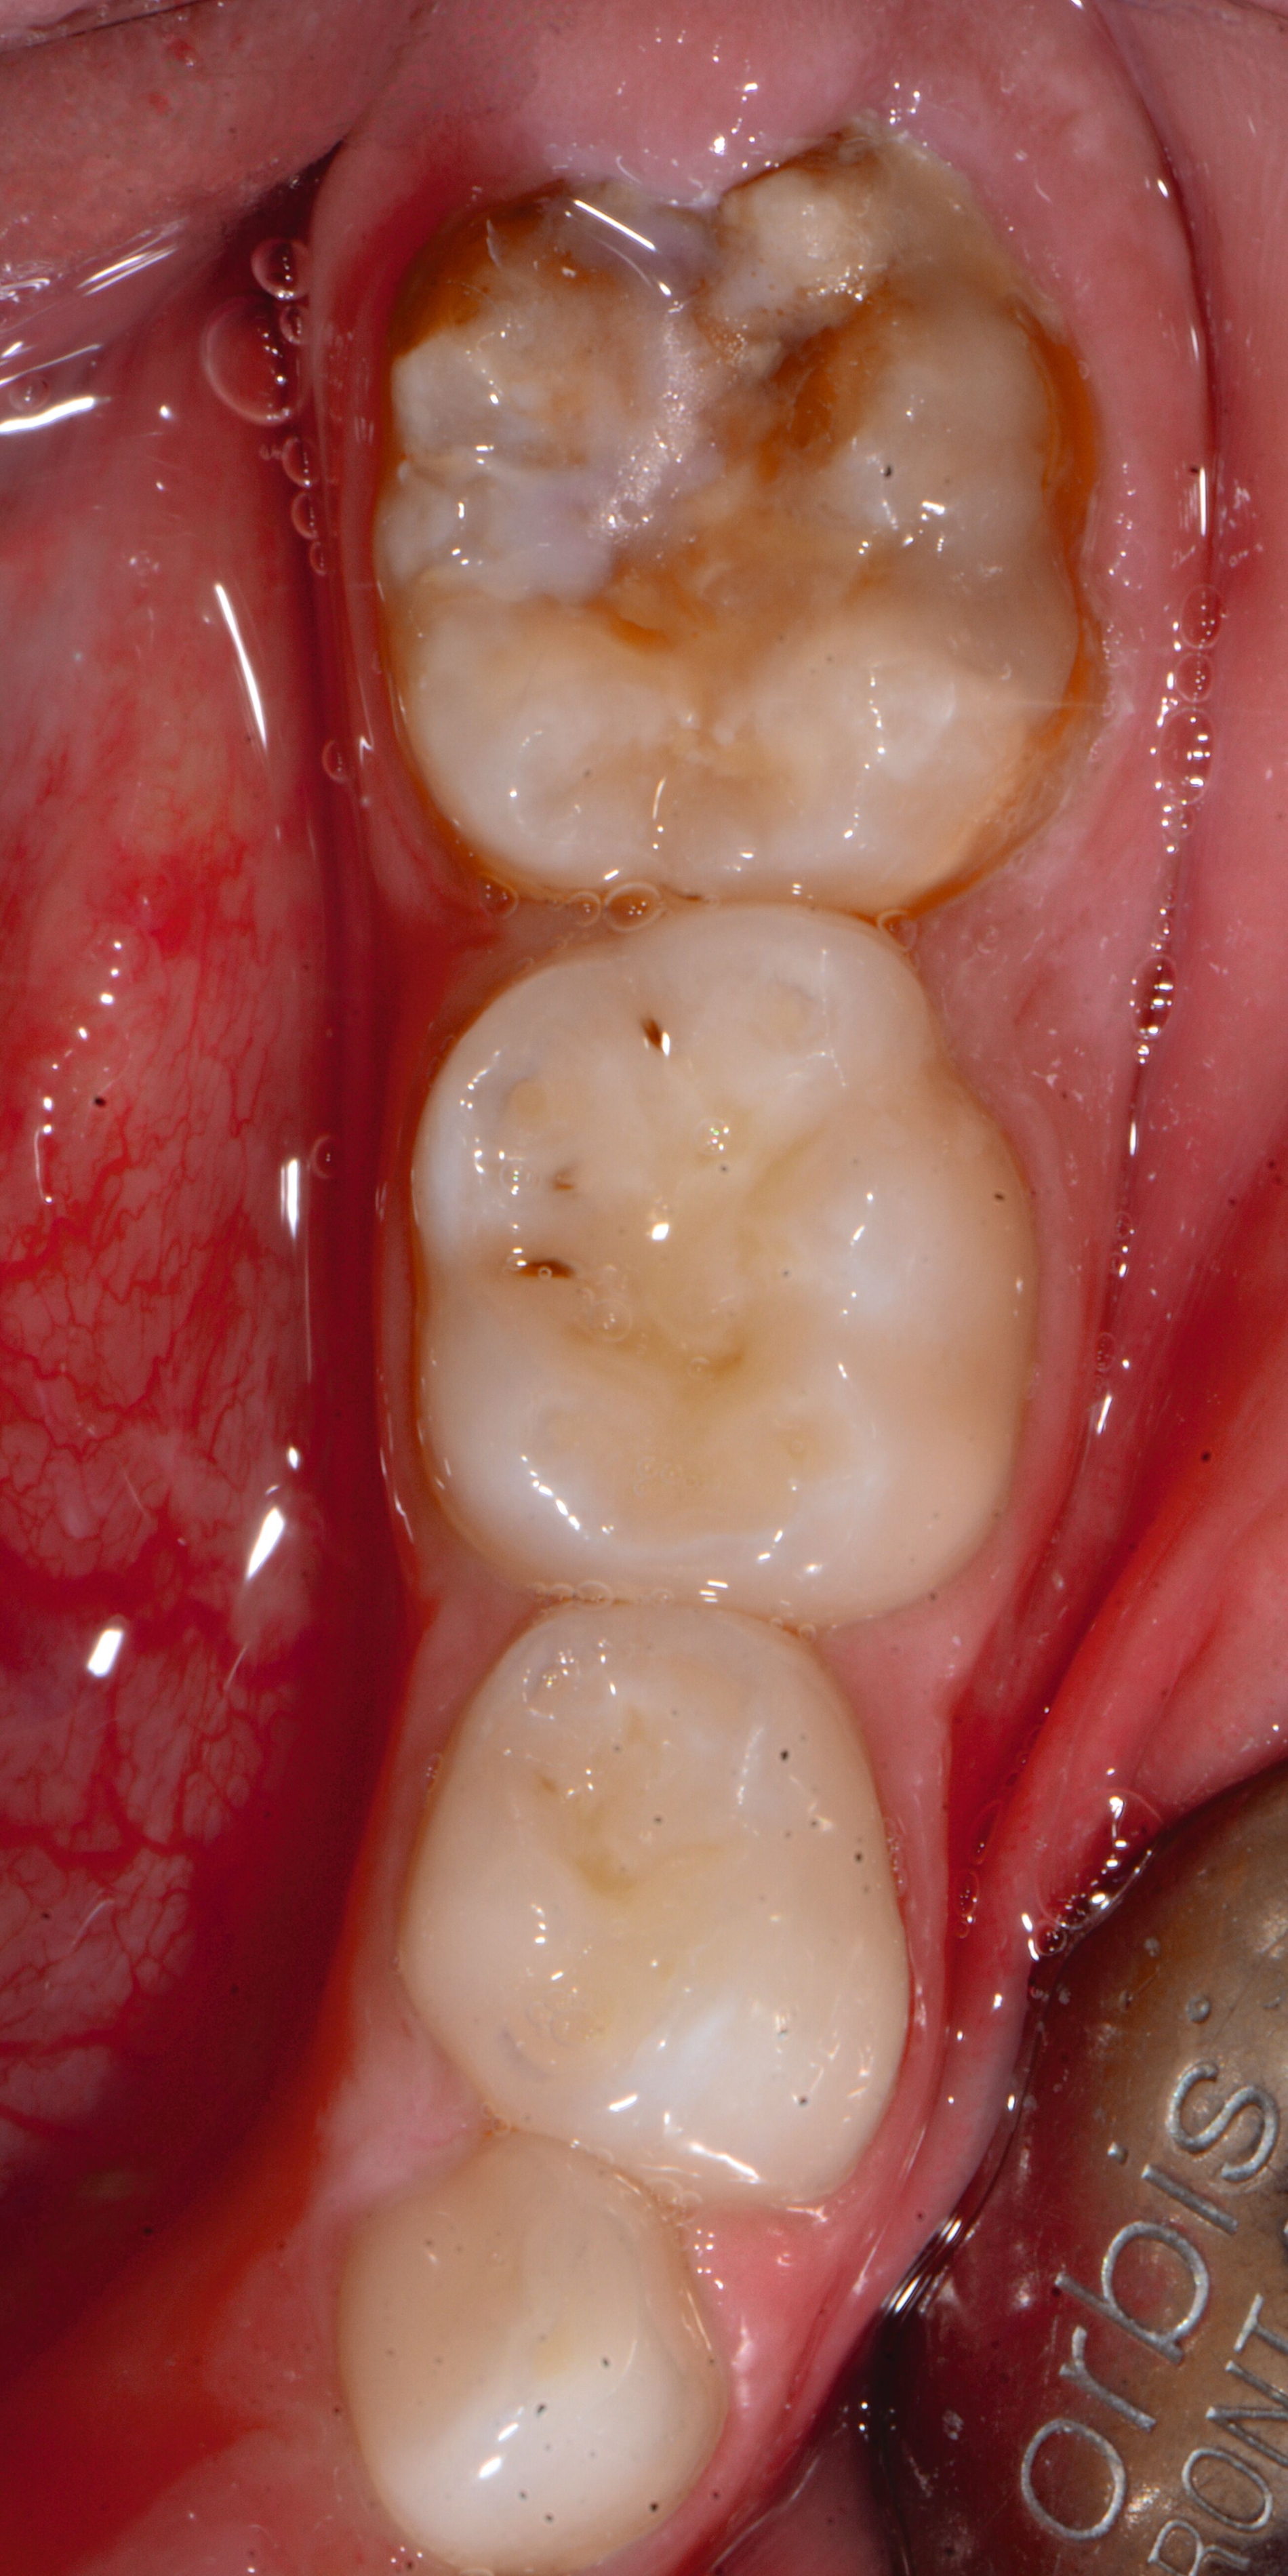

An umfangreich hypomineralisierten Zähnen können Schmelzeinbrüche (engl.: „enamel breakdown“ oder „enamel desintegration“, Abbildung 5) auftreten [Lygidakis et al., 2010; 2022]. Da diese oftmals die Folge einer fehlenden Belastungsfähigkeit des Zahnschmelzes sind und erst nach der Einstellung der Zähne in die Okklusion auftreten, werden sie auch als posteruptive Schmelzeinbrüche bezeichnet. Sie sind häufig im Bereich der Kauflächen beziehungsweise Höcker der Molaren zu finden, führen zur Dentinexposition und damit einhergehend zu ausgeprägten Hypersensitiven insbesondere bei Kindern, deren Zähne gerade erst durchgebrochen sind [Linner et al., 2021].

Bei post- beziehungsweise präeruptiven Oberflächendefekten ergibt sich in einigen Fällen die Indikation zur Restauration dieser MIH-Zähne. Unter Verweis auf die Lokalisation von MIH-bedingten Hypomineralisationen außerhalb der typischen Kariesprädilektionsstellen – zum Beispiel okklusale Fissuren und Grübchen oder Approximalflächen – werden diese als „atypische Restaurationen“ (engl.: „atypical restoration“, Abbildung 6) klassifiziert. Als ein weiteres Erkennungsmerkmal gilt die Präsenz von Hypomineralisationen im Bereich der Restaurationsränder. MIH- und kariesbedingte Restaurationen können und sollten sicher voneinander abgegrenzt werden.

Für die Dokumentation und Klassifikation der MIH wurden verschiedene Systeme vorgeschlagen. Als historisch und veraltet gilt der (modifizierte) DDE-Index. Demgegenüber haben die Kriterien der EAPD – abgegrenzte Opazitäten (Abbildung 3 und 4), Schmelzeinbrüche (Abbildung 5), atypische Restaurationen (Abbildung 6) – mittlerweile die weiteste Verbreitung gefunden. Diese wurden 2003 erstmals zur Beschreibung der MIH auf empirischer Basis publiziert [Weerheijm et al., 2003] und den Jahren 2010 und 2022 im Rahmen der damaligen MIH-Workshops bestätigt [Lygidakis et al., 2010; 2022].